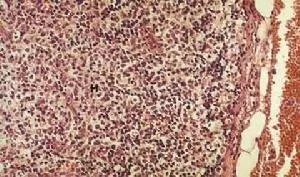

病理学

该病一般由活体组织切片诊断。由于菊池病是一种自限性疾病(self limiting illness根头字根块依指),会因与霍奇金病的相似而误诊。抗核酸抗体、抗磷脂抗体、类风湿因子复脚检验常为阴性。